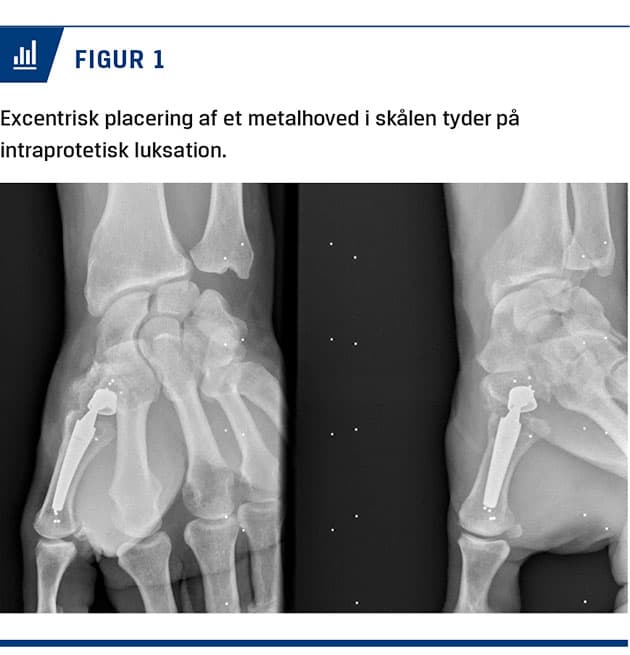

Ved femårskontrollen fortalte patienten, at han med jævne mellemrum havde en følelse af, at det klikkede og smuttede ved protesen, hvilket kunne give smertejag. På en røntgenoptagelse af rodleddet så man, at ledhovedet på protesen ikke var centraliseret i ledskålen i trapezium, hvilket gav mistanke om, at polyethylenhovedet kunne være lukseret (Figur 1). Ved gennemgang af de tidligere røntgenbilleder kunne man nu se, at ledhovedet allerede ved toårskontrollen stod excentrisk i skålen som tegn på, at polyethylenhovedet var lukseret. Patienten blev reopereret, og man fandt polyethylenhovedet helt separeret fra metalhovedet og roteret. Metalhovedet på protesen var helt slidt ned på den ene side som tegn på, at tilstanden havde stået på gennem længere tid. Ledskålen var fortsat fastsiddende i trapezium, og den havde overraskende ikke tegn på uhensigtsmæssigt slid. Man kunne derfor nøjes med at skifte dual mobility-ledhoved og -hals på protesen.

En kendt komplikation i forbindelse med såkaldt dual mobility-proteseartikulation i hofteleddet er, at det store plastikhoved hopper af det lille metalhoved, hvilket kaldes en intraprotetisk luksation [5]. Dette vil kunne ske ved andre protesetyper, hvor man anvender denne artikulationsform. Ved rutinekontrollen efter to år hos patienten i sygehistorien fokuserede man på de sædvanlige tegn på løsning af protesekomponenterne med radiologiske opklaringer og ændring af skålens placering, da det er den hyppigste årsag til smerter og klikkende fornemmelse ved rodledsproteser. Ved proteseluksation er ledhovedet normalt ude af skålen, og man overså derfor de radiologiske tegn, hvor metalhovedet stod excentrisk i skålen, hvilket ellers er et sikkert tegn på intraprotetisk luksation eller slid på polyethylenlineren. Intraprotetisk luksation i en rodledsprotese i tommelfingeren er ikke tidligere beskrevet i litteraturen, men denne sygehistorie understreger vigtigheden af, at man er opmærksom på, at der ved overførelse af artikulationsformer fra en type led til en andet er risiko for, at tilsvarende komplikationer følger med – i dette tilfælde en intraprotetisk luksation.